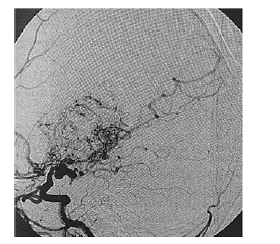

Paciente de 16 anos de idade, do sexo feminino, de asscendência japonesa, com deficits neurológicos progressivos iniciados ainda na infância, tem diagnóstico prévio de anemia falciforme. Realizou exame complementar de imagem do encéfalo, apresentado na reprodução acima. Há suspeita de doença de Moyamoya.

Em relação ao caso descrito, julgue os itens a seguir.